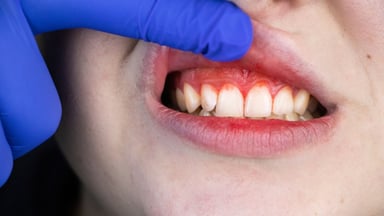

Dấu hiệu nhận biết của bệnh là những tổn thương bên trong miệng của bé: xuất hiện những mảng trắng dày nổi lên trên bề mặt lợi, niêm mạc má, vòm miệng… Hơn thế, các bề mặt tổn thương có thể còn quan sát thấy tình trạng rớm máu.

Khi mắc viêm loét hoại tử cấp tính, trẻ thường có biểu hiện đau liên tục, dữ dội và xuất hiện tình trạng hôi miệng. Nguyên nhân là bởi miệng của bé bị tích tụ vi khuẩn và mô hoại tử. Tổn thương ban đầu xuất hiện ở nhú lợi rồi dần lan rộng ra các bờ lợi ở bề mặt lưỡi và bề mặt môi.